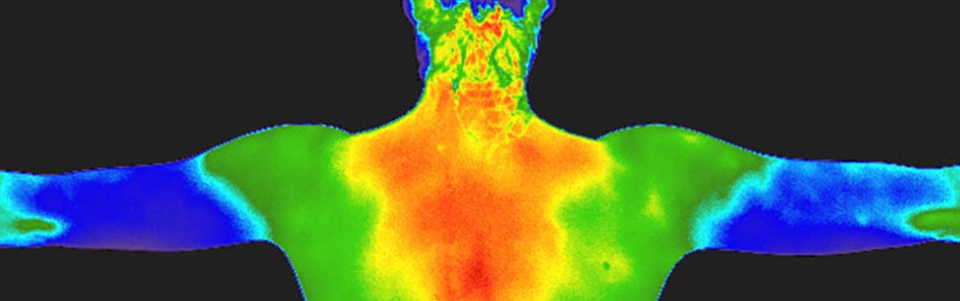

Digital Infrared Thermal Imaging

Digital Infrared Thermal Imaging, or DITI, is a totally non-invasive, painless procedure with no radiation and no contact with the body. It uses an infrared camera with a highly accurate heat sensor to detect differences in temperature in the body.